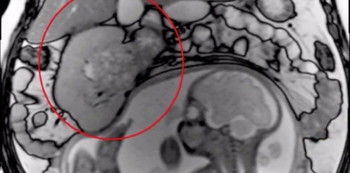

tumour in pregnancy

Regular MRI scans showed the tumor was right next to Susan’s unborn baby. | Image courtesy: SWNS/screengrab

O’Flanagan explains why. “Luckily regular MRI scans showed that the tumor wasn’t growing so teams at Guy’s and St Thomas’ decided that it was safe for me to continue with the pregnancy while being closely monitored. As the baby grew, and with the pressure from my tumor, it became increasingly uncomfortable and painful, and I felt ill all the time.”

“One of the scans even showed the baby kicking the tumor,” she added.